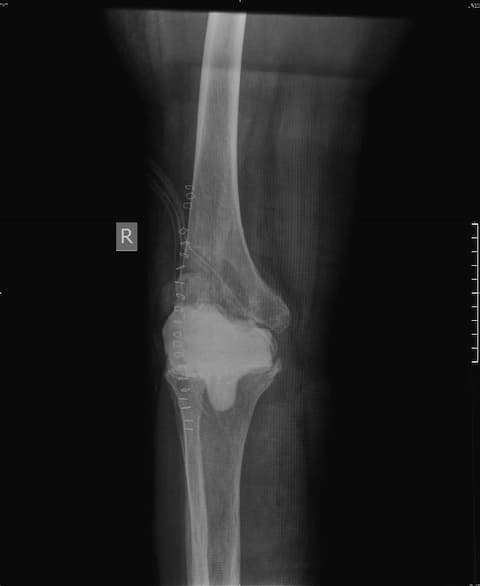

Тохиолдол танилцуулга 4.

Өвчтөн: Б, 73 настай, эмэгтэй

Урьд нь хийгдсэн мэс заслын түүх: 2016 онд өвдөгний хиймэл үе суулгах мэс засал хийлгэсэн. Мэс заслын дараа халдварын хүндрэл гарсан

Хоёрдахь мэс засал: Хиймэл үеийг авч, оронд нь антибиотиктэй цемент хийсэн. Халдварын хүндрэлийн улмаас ясны том хэмжээний дутмагшил үүссэн.

Сэргээн засах мэс засал: Зүүн дунд чөмөг-өвдөгний үе сэргээх тусгай протез суулгах мэс засал.

Үе дайрсан ясны анхдагч хавдар, ясны дутмагшлын үед хийгдэх мэс засалimg17Үе дайрсан ясны анхдагч хавдар, ясны дутмагшлын үед хийгдэх мэс засалimg18

Зураг 1. Сэргээн засах мэс заслын өмнөх рентген зураг. Эгц урд, хажуугаас авсан байдал.